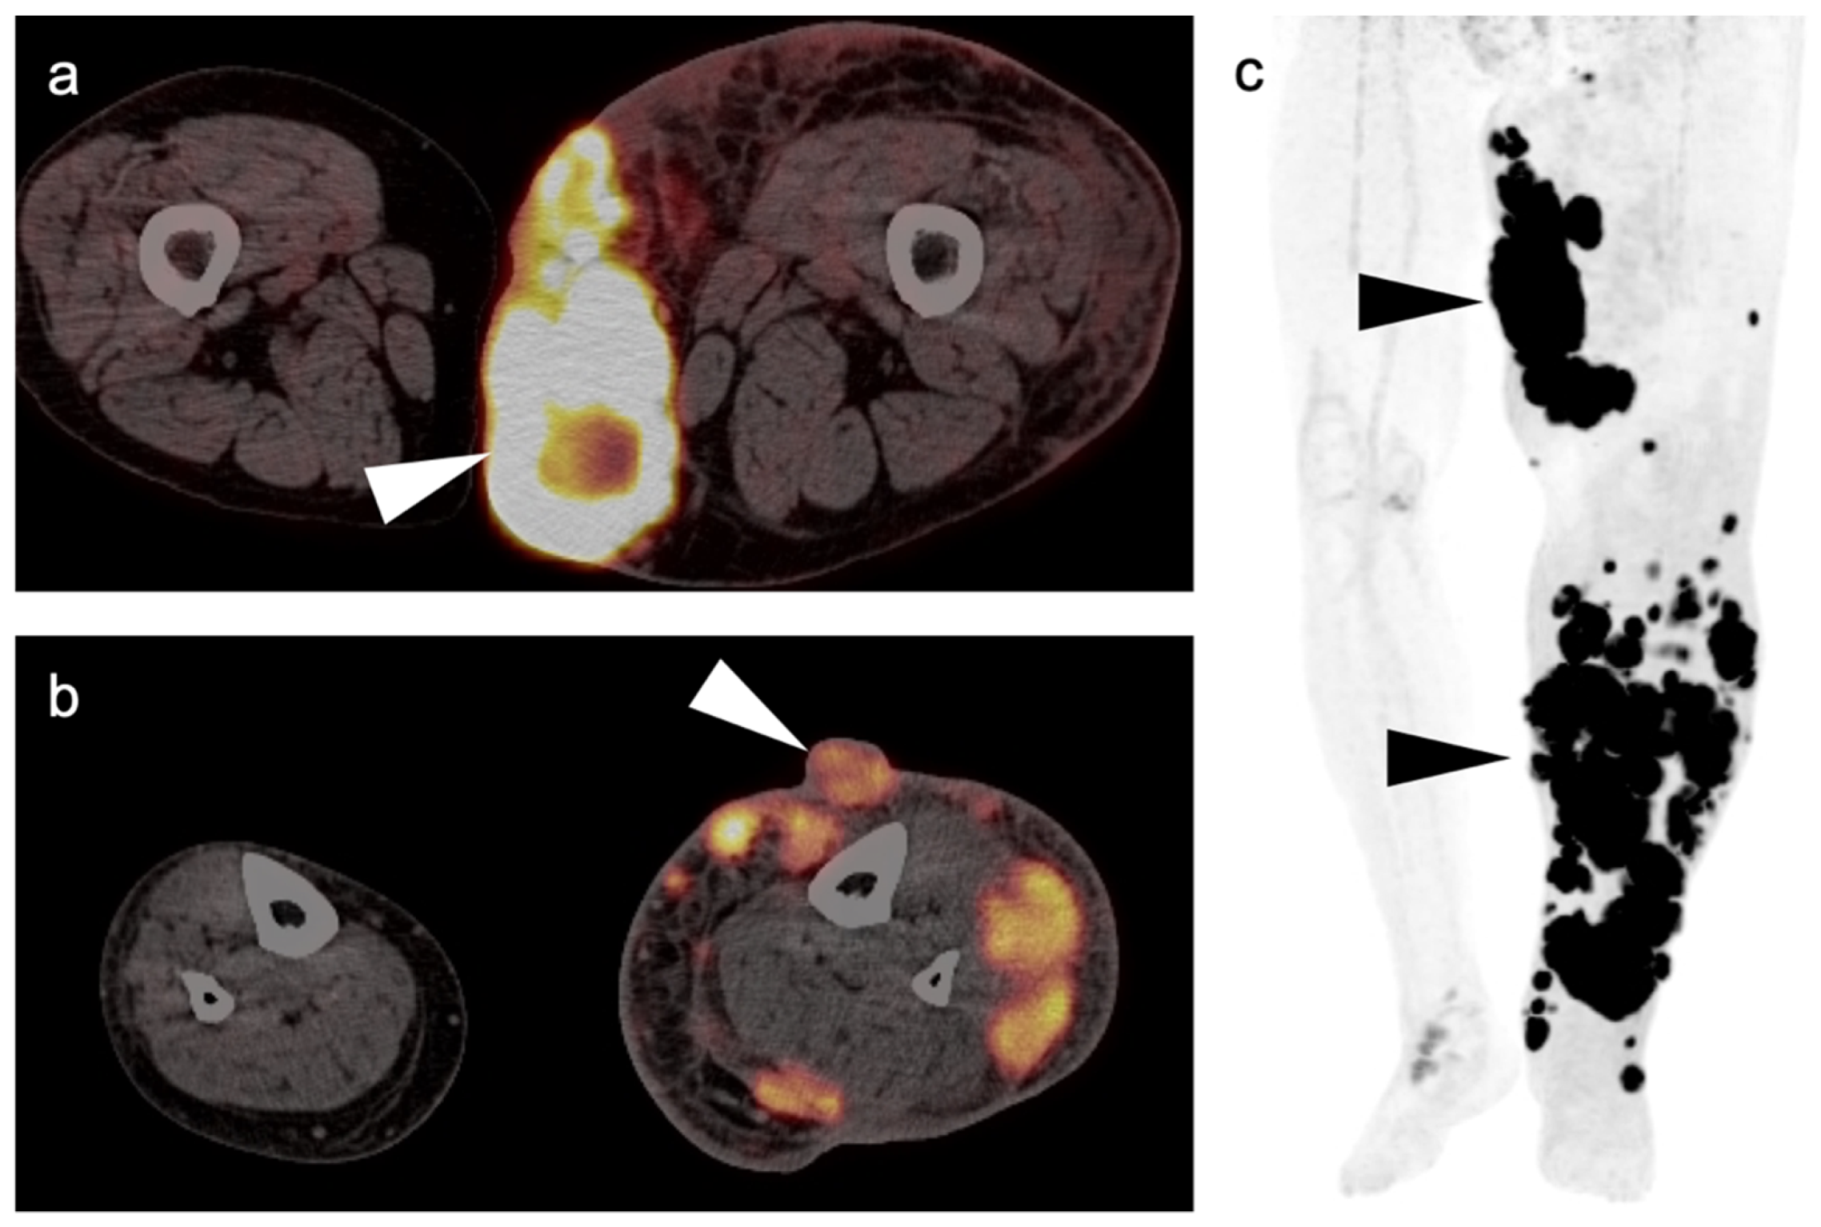

3. Sarcomas

3.1. Soft Tissue Sarcomas

3.1.1. Undifferentiated Pleomorphic Sarcoma

3.1.2. Leiomyosarcoma

3.1.3. Angiosarcoma

3.1.4. Kaposi Sarcoma

3.1.5. Rhabdomyosarcoma

3.1.6. Liposarcoma

3.1.7. Synovial Sarcoma

3.1.8. Nerve Sheath Tumors

3.2. Bone Sarcomas

3.2.1. Chondrosarcoma

3.2.2. Osteosarcoma

3.2.3. Ewing Sarcoma